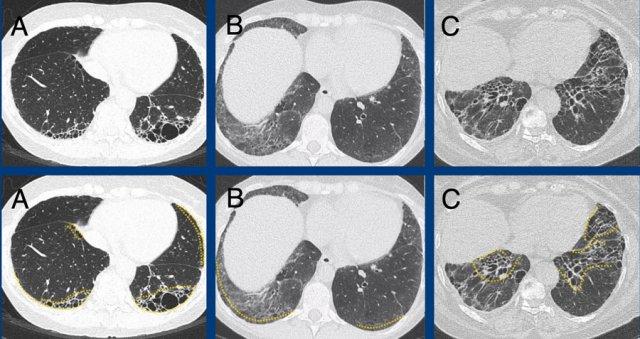

Hình ảnh cho thấy bệnh phổi xơ hóa với sự biến dạng của tiểu thùy thứ cấp, mất thể tích và giãn phế quản do co kéo (màu xanh lá là bình thường, màu vàng là bất thường).

Các

hình ảnh minh họa các ví dụ về lưới không xơ hóa do dày thành kẽ trong phù phổi (A), ung thư biểu mô di căn đường bạch huyết (B), và浸润 bạch cầu ái toan trong u hạt bạch cầu ái toan kèm viêm đa mạch [EGPA,

trước đây gọi là hội chứng Churg-Strauss] (C).